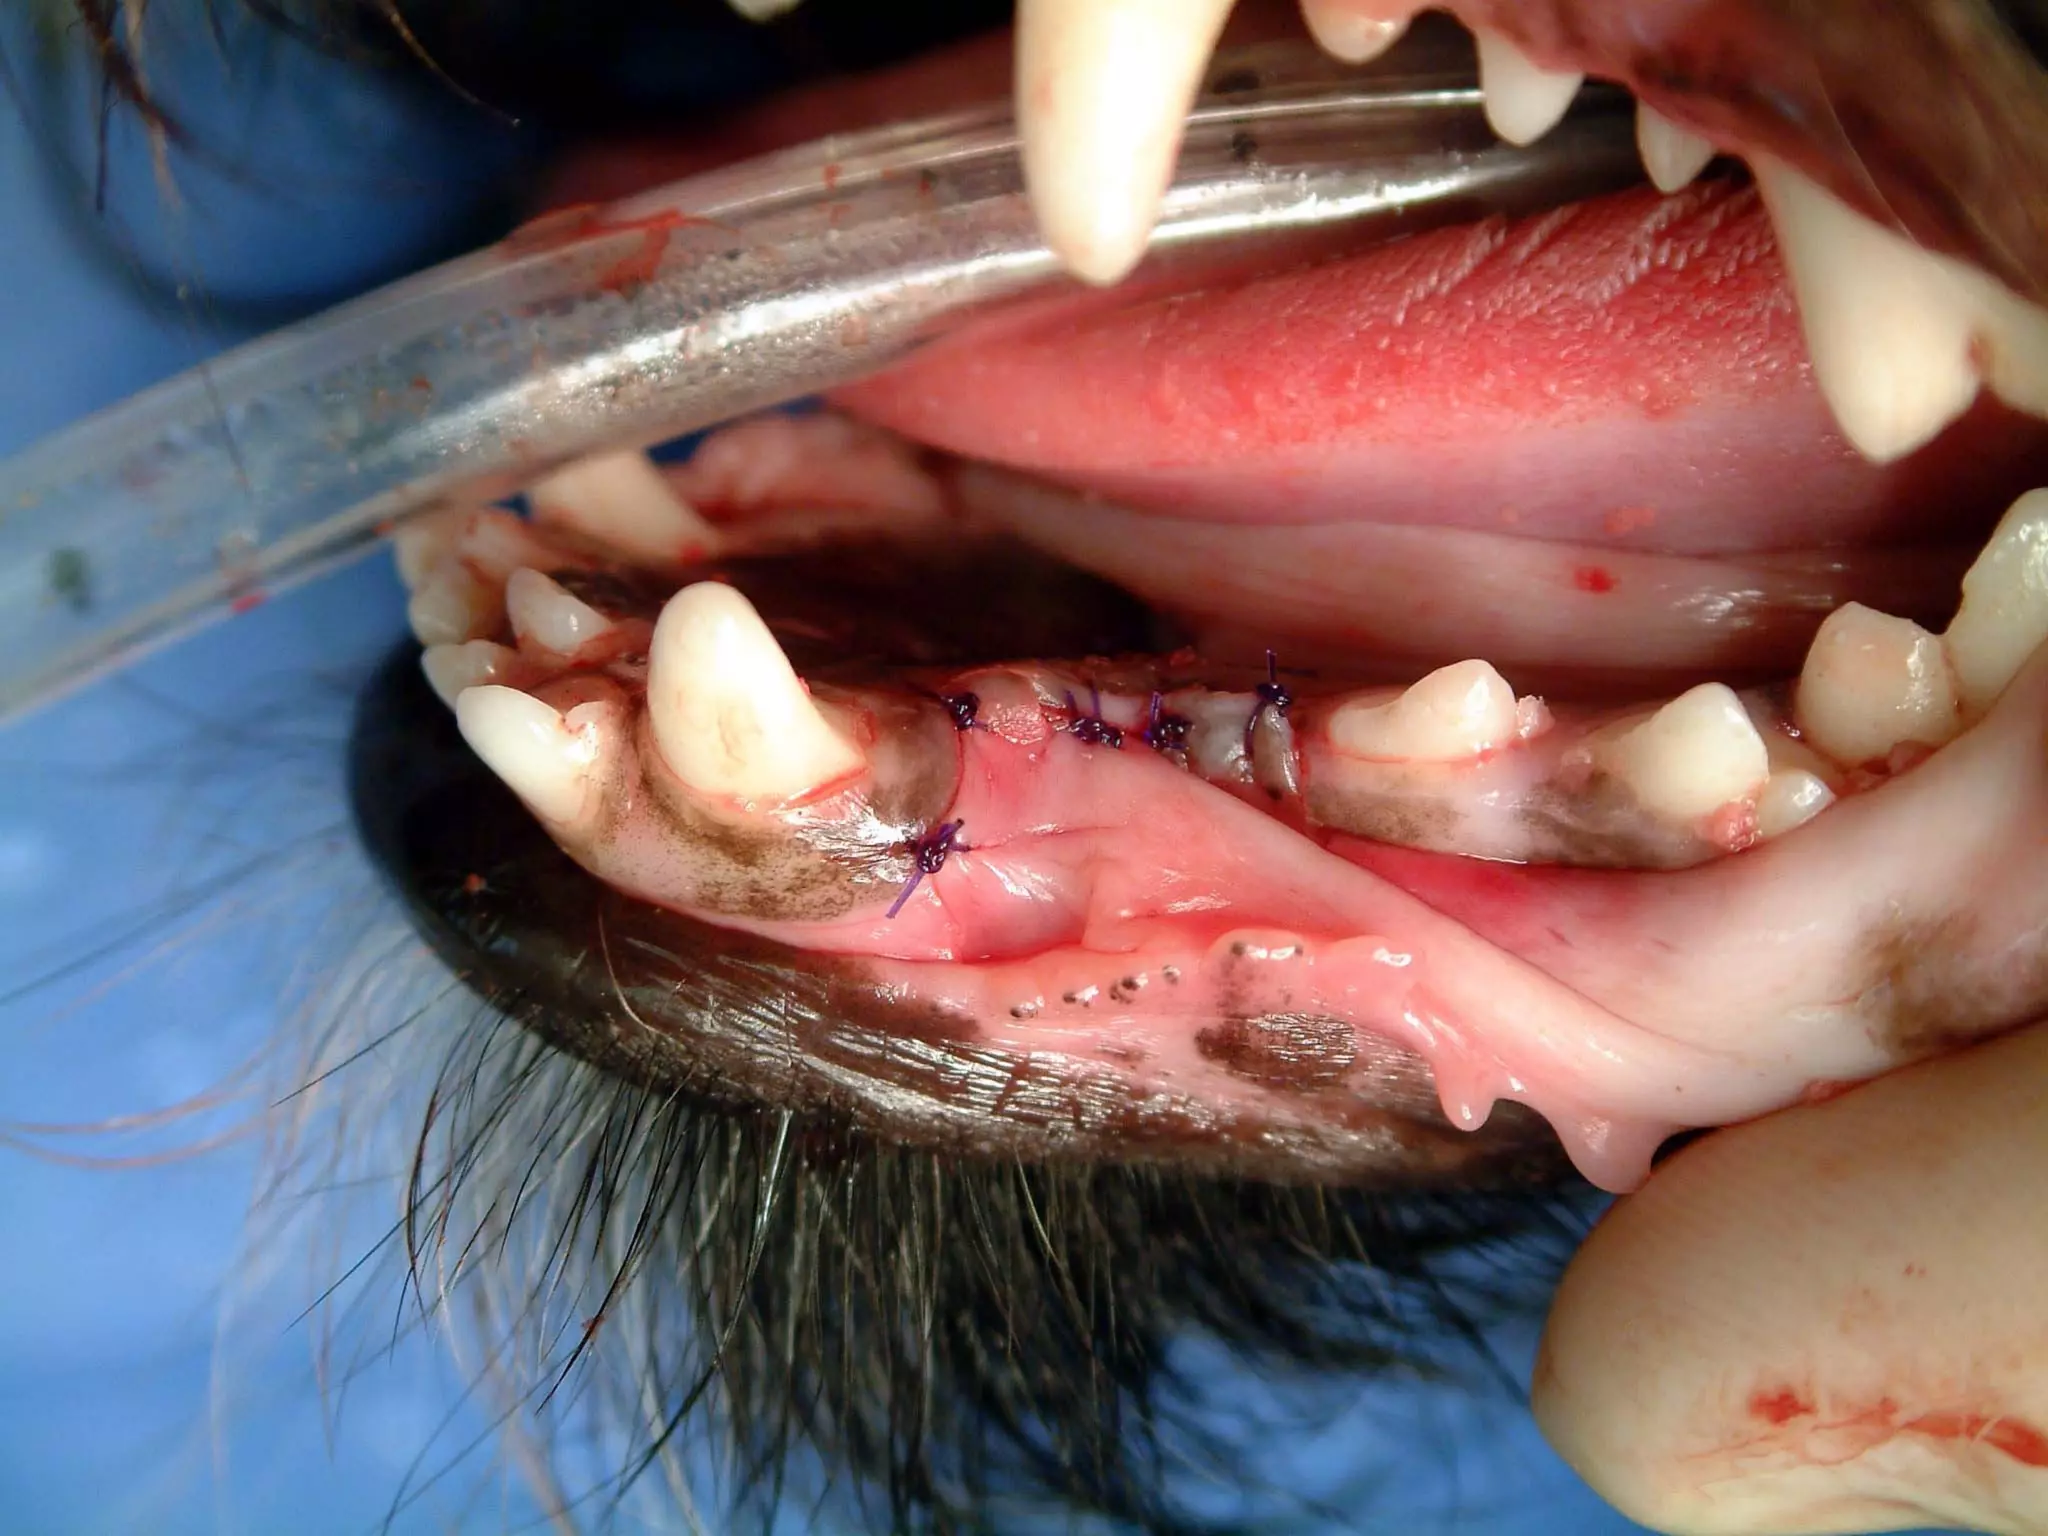

Take a look at the left mandible on this cat.

Text

20

What is the most likely cause of this process

in this cat?

What is the only definitive treatment?

21

• 20.

Take a lookat the left mandible on this cat. Text 20

• 21.

What is themost likely cause of this process in this cat? What is the only definitive treatment? 21